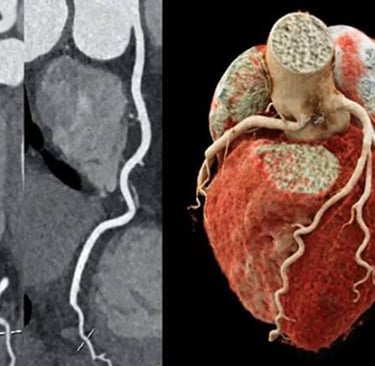

👉 La angiotomografía coronaria

Una técnica no invasiva que permite visualizar las arterias del corazón con gran precisión, sin necesidad de introducir catéteres dentro del cuerpo.

La angiotomografía coronaria es un estudio de imagen avanzado que utiliza tomografía computarizada (TC) junto con contraste intravenoso para obtener imágenes detalladas de las arterias del corazón.